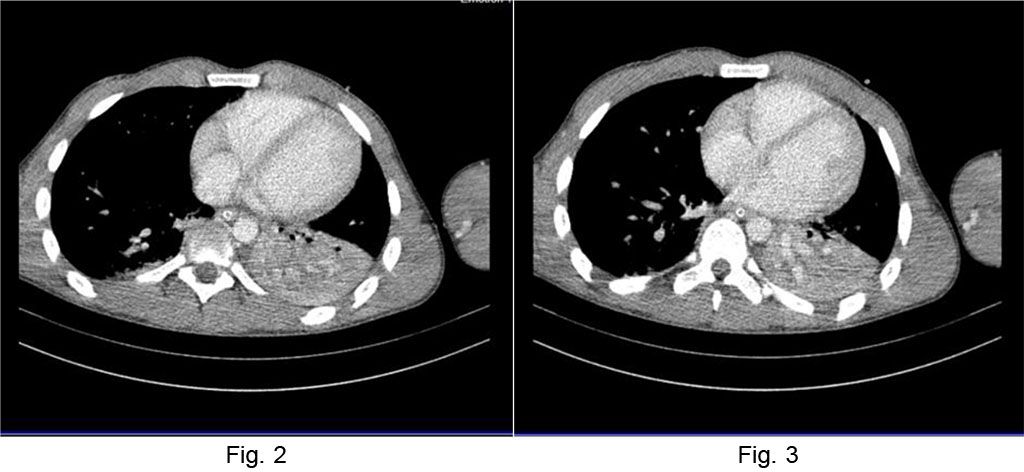

CT examination revealed focal alveolar filling without aerial bronchogram, which contained small aerial inclusions, with normal contrast of the vascular structures, visible at the level of the lower left lobe, which moderately exerted a retractable effect on the fissure – atelectasis of the lower left lobe. Small amount of left pleural fluid in basal rear area, ~ 5mm (Figures 2, 3).

Fig. 2 Chest CT atelectasis

of the lower left lobe Fig.

3 Left

pleural fluid layer.

Source: Authors' own work